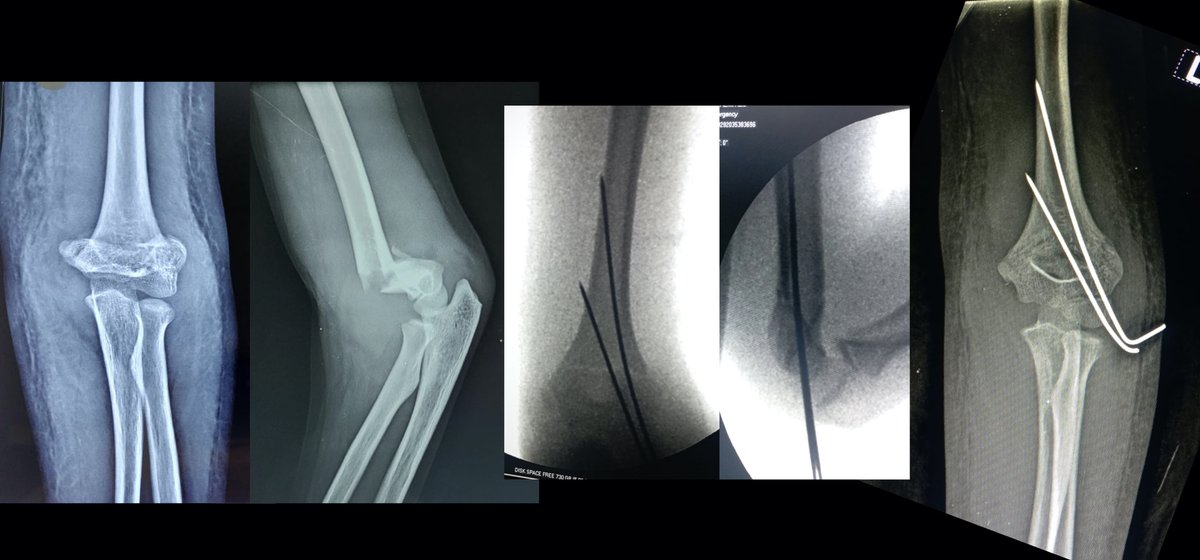

What’s your unpopular medical opinion that would land you in this position? Drop it in this thread

Healthcare: Netherlands vs India 🇳🇱 1 week to get the appointment. Come back after 2 weeks of simple medicines level 2 medicine for 2 weeks. Still not sure about the next steps. 🇮🇳 Visit doctor. 10 mins - CT scan 20 mins - prescribes surgery 2 days later - surgery done A week - recovering. 2 months later: Hmmm, maybe, just mayyybeee I didn't need to do that surgery.